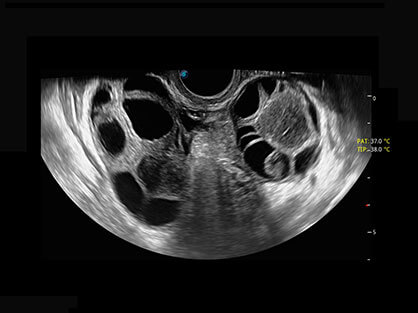

• AVC Follice卵泡自动测量

卵泡结构的自动识别和测量,可显示多组测量数据。

大角度腔内容积探头,可完整包络子宫及盆底结构,充分展示组织结构毗邻关系。